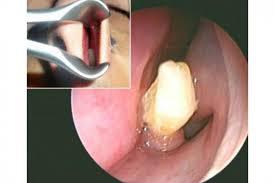

Zhang Binsheng, de la ciudad china de Harbin, acudió a los médicos la semana pasada luego de sufrir una grave obstrucción en sus fosas nasales por tres meses. El hombre se sorprendió al descubrir que el bloqueo lo causaba una pieza dental la cual perdió durante un accidente cuando era niño (cerca de 20 años) y según el doctor, quien extrajo la pieza, de alguna manera logró enraizar y crecer. Al parecer, no fue rechazado como un objeto extraño por el organismo y eso evitó detectarlo.